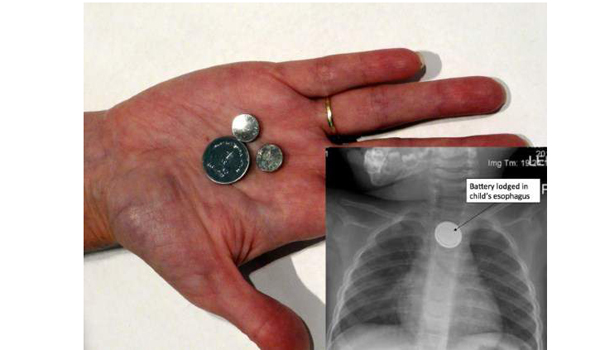

4. Baterai Seukuran Kancing

Baterai seukuran kancing sering digunakan pada jam tangan atau pada remote control. Mainan anak-anak dan berbagai benda lain yang memerlukan baterai berukuran kecil.

Namun siapa sangka jika benda ini masuk dalam daftar gadget yang paling banyak menyebabkan kematian.

National Capital Poison Center (NCPC) di Washington, DC mencatat. Bahwa sejak 1985 telah lebih dari 60.000 orang yang menelan baterai seukuran kancing tersebut.

Lebih dari 3.500 orang mengalami cidera, dan 9 diantaranya bahkan mengalami kematian. Kasus tersebut rata-rata terjadi pada anak-anak yang usianya masih berada di bawah enam tahun.

Saat baterai tersebut tertelan oleh anak-anak, maka dapat terjebak pada tenggorokan. Akibatnya anak-anak tersebut bisa mengalami luka bakar kimia yang parah.

Efeknya bisa dalam beberapa menit pasca baterai tersebut tertelan, setelah dua jam dapat membakar lubang kerongkongan dimana baterai tersebut telah tersangkut.

Menyikapi hal ini, maka orang tua harus ekstra hati-hati. Setidaknya jangan sampai meletakan baterai berukuran kecil pada daerah yang mudah dijangkau oleh anak-anak.